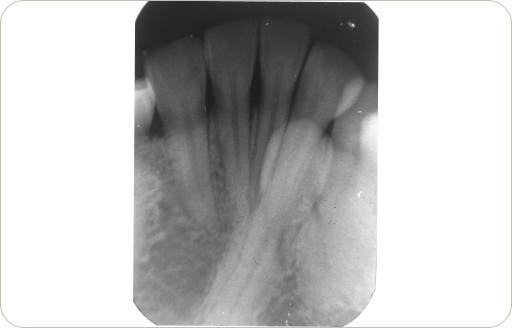

Especialistas en Medicina y Patología Bucal 2010

2